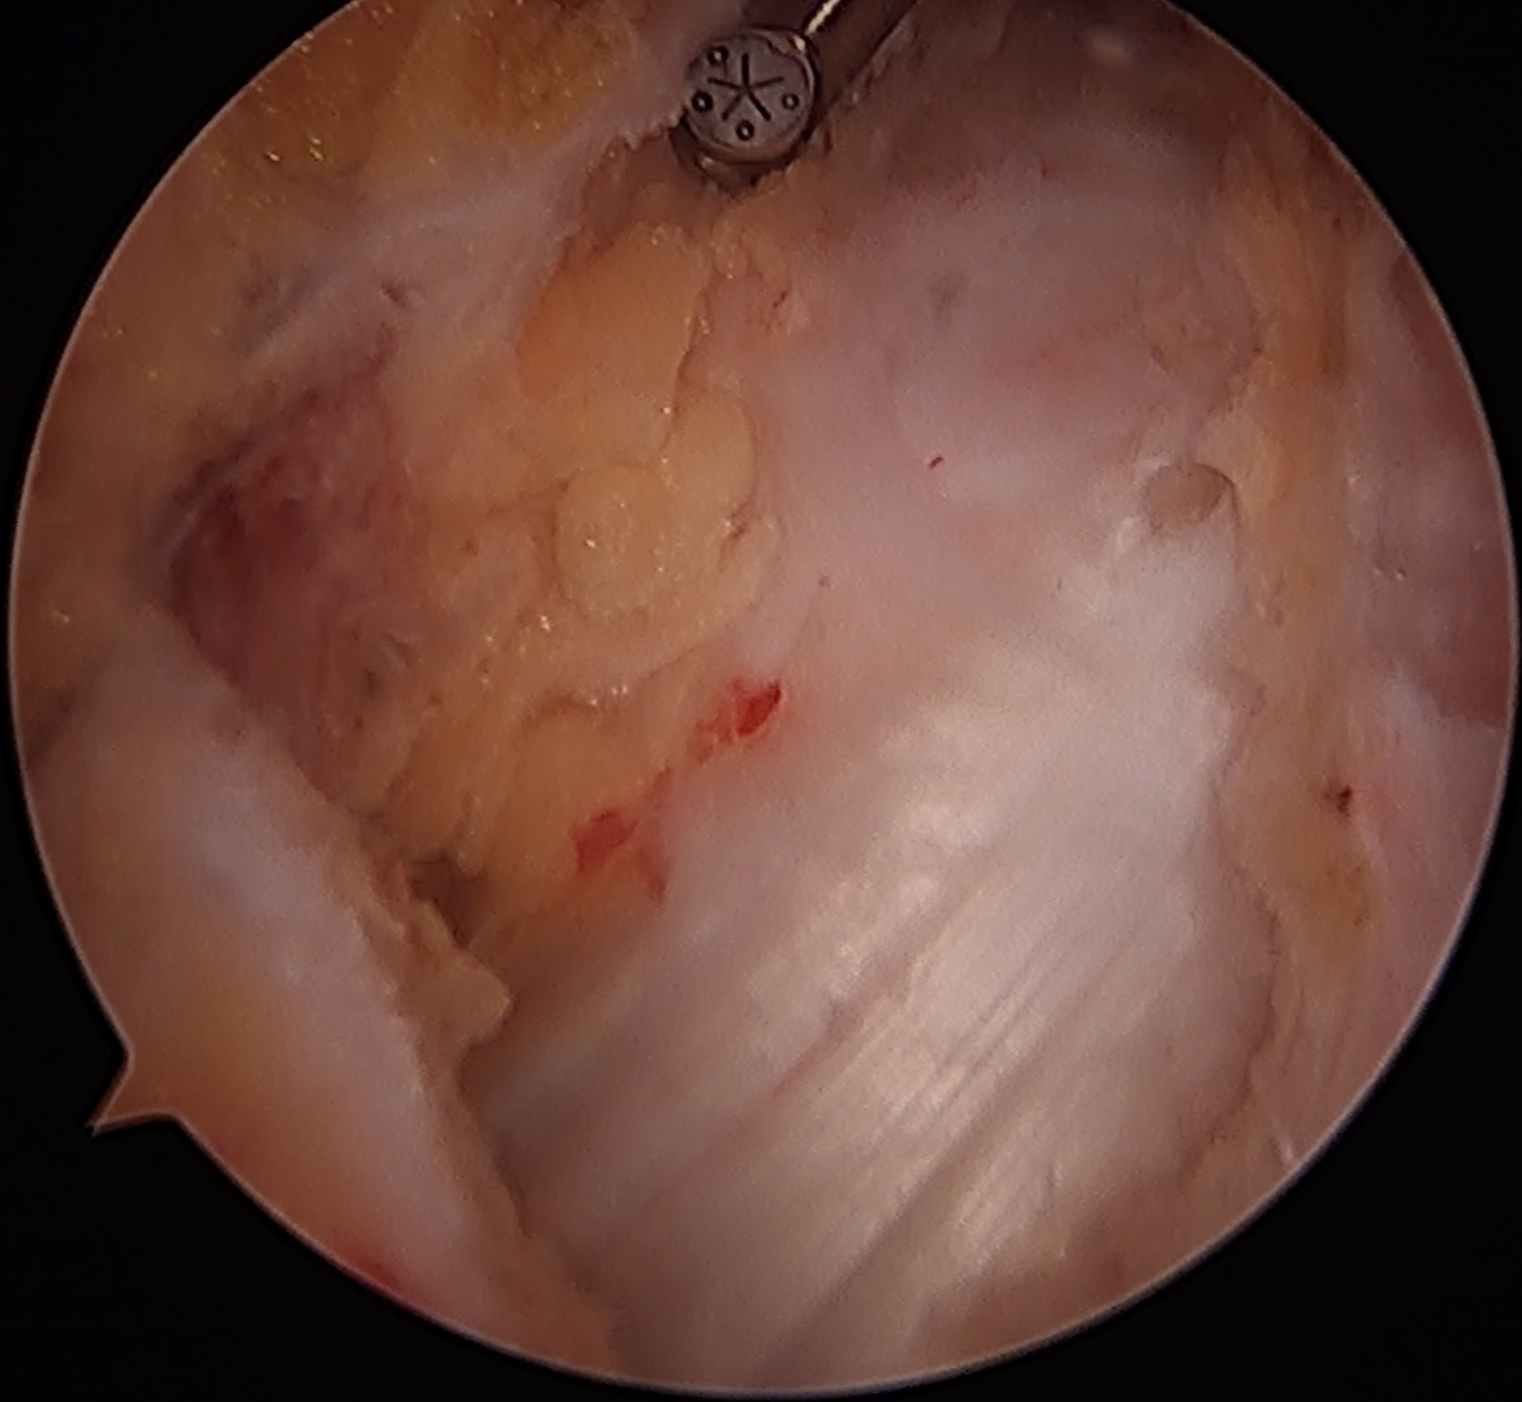

ITB vertical split / cruciform release + trochanteric bursectomy

Arthroscopic technique article

ITB band Longitudinal split

Cruciform release anteriorly Bursectomy over abductors

Results

Drummond et al Arch Orthop Traum Surg 2016

- endoscopic longitudinal ITB release with trochanteric bursectomy

- 49 patients mean age 60

- 20% not satisfied